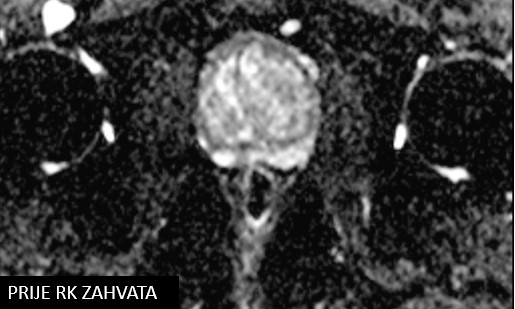

Bolesnik, rođen 1954.

Dijagnoza:

Npl prostatae

Biopsio prostatae (1/2022)

PHD: adenocarcinoma, Gleason 3+3, grade group 1

iPSA 6,423

SABR npl. prostatae (28.06.- 07.07.2022.)

Rezultat - 15 mjeseci nakon RK